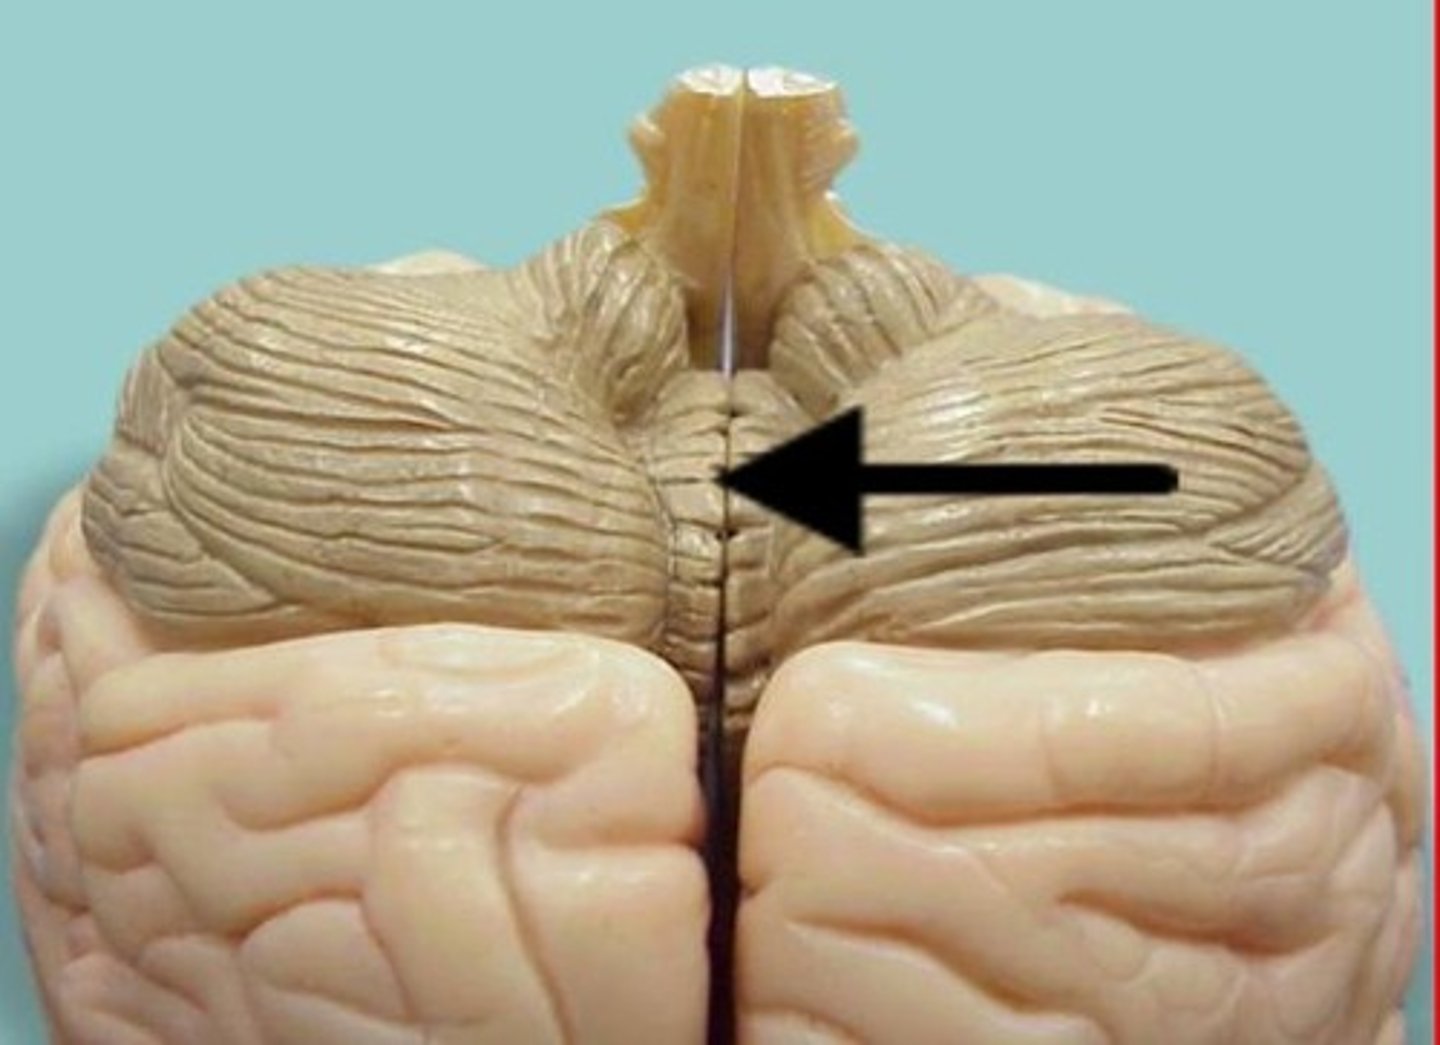

vermis